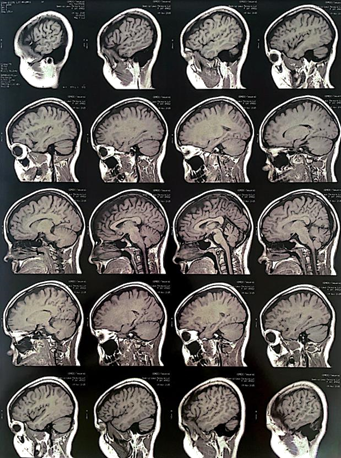

When she was 13, still on her medication, she had a generalized tonic-clonic seizure. When questioned about it, she said she was not taking her medicine at the right time, or taking it at all, and that she was having a lack of sleep. In the Emergency Room was made a blood screening that showed Valproic Acid (58mcg/mL) in her blood. She did another ECG (Figure 2), which still presented compatible changes with AS, and an MRI (Figure 3) with contrast that did not reveal any damage. The conduct was taking the medication on time and having enough sleep.

Figure 2 ECG presenting compatible changes with AS.

Figure 3 Magnetic resonance image scan of the brain.